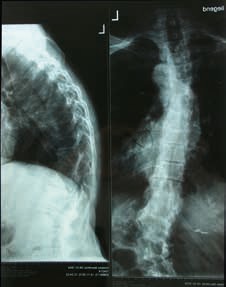

Die adulte Skoliose ist oft mit anderen Erkrankungen verbunden, die sich in der Beschwerdelage des Patienten durchaus als führend darstellen können. Krankheiten und Einschränkungen wie beispielsweise Parkinson, Osteoporose, Schrittmacher, Rollstühle oder Sondenzugänge erfordern individuelle Lösungen durch die Orthopädie-Technik, die sich meistens umsetzen lassen 9. Patienten mit einem Korrekturkorsett berichten von einer Entlastung oft nur beim Tragen des Korsetts während alltäglicher Tätigkeiten und auch nur stundenweise. Die Tragedauer ist grundsätzlich geringer als bei einer idiopathischen adoleszenten Skoliose, bei der das Korsett wachstumslenkend 23 Stunden pro Tag getragen werden muss. Ein begrenzender Umstand ist oft die schon sehr rigide Skoliose, die keine vollständige Korrektur mehr zulässt. Hier gilt es einen für den Patienten gangbaren Weg zu erarbeiten (Abb. 2a u. b).